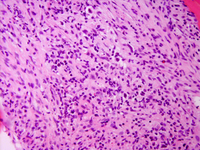

Four months later, PET-CT identified a new FDG-avid left axillary mass. Excisional biopsy showed complete effacement of nodal architecture by a polymorphous infiltrate containing scattered Reed–Sternberg and Hodgkin cells. These cells expressed CD30, CD15, MUM1, PAX5 (weak), and cyclin D1, while negative for ALK, BCL6, CD20 and EBER-ISH. The background was rich in T cells with a mixed CD4/CD8 phenotype, intact expression of CD2, CD5, CD7, and no evidence of follicular helper T-cell phenotype. Follicular dendritic cell meshwork was absent by CD21/CD23. The findings were diagnostic of classic Hodgkin lymphoma (CHL).

Although no morphologic or immunophenotypic features of MCL were present, FISH confirmed persistence of the IGH::CCND1 rearrangement within Hodgkin/Reed–Sternberg cells. Next-generation sequencing detected no pathogenic variants, and ClonoSeq remained negative. The patient received Adriamycin, Bleomycin, Vinblastine, and Dacarbazine (ABVD) and achieved complete remission.